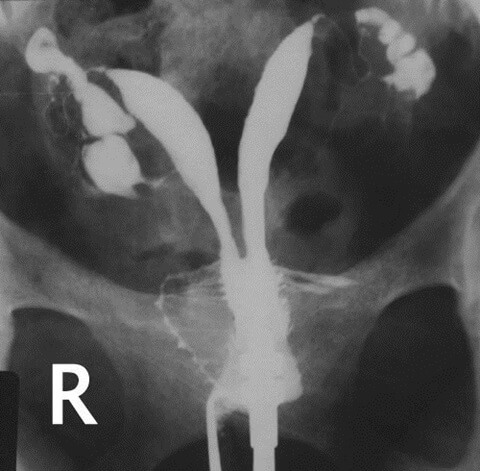

Normal rahim filminde üçgen şeklinde bebeğin yerleşeceği yer ve bu üçgenin üst iki köşesinden yumurtalıklara doğru giden çok ince iki adet tüp izlenmektedir. Aşağıda normal rahim filmi ve normal olmayan rahim flimlerini inceleyebilirsiniz.

Resim 1-) Normal tüpleri açık rahim filmi

Resim 5-) Çift rahim görüntüsünü gösteren HSG